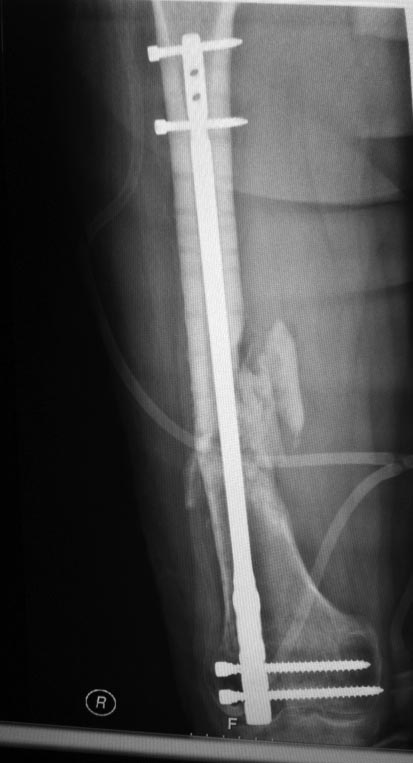

[Ortho] ЛОЖНЫЙ СУСТАВ ПОСЛЕ БИОС

еще снимки